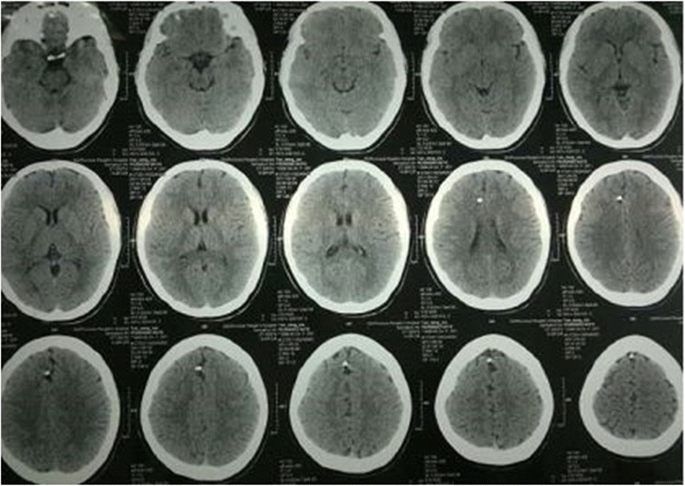

On admission she was alert and her neurological examination was normal, there were no focal neurological examination findings. There was no previous history of absence seizure and her past medical history was unremarkable. She reported no history of head trauma or injury. Laboratory finding of the cerebrospinal fluid were normal. Blood routine, urine routine test were normal. Skull radiography revealed the presence of a metal foreign body situated in a craniocaudal direction along the midline (Fig. 1a and b). Also, Computerized tomography (CT) of the brain was performed and showed a metal foreign body embedded in the right frontal lobe, passing through the sagittal sinus (Fig. 2). Intracranial bleeding, arteriovenous malformation and any intracranial occupying lesion were not detected by the CT scan. CTV/CTA reconstruction showed close proximity of metal foreign body and the major blood vessels (Fig. 3).

Surgical positioning was very accurate with help of the intraoperative navigation. Intraoperative fluorescein angiography displayed venous drainage across the sagittal sinus in order to avoid its damage. CT scan on the following morning of surgery was taken and 1 year post surgery CT is shown in Fig. 6. The foreign body was removed successfully without any complications. The patient has been followed for more than 3 years and has remained asymptomatic with impeccable recovery.